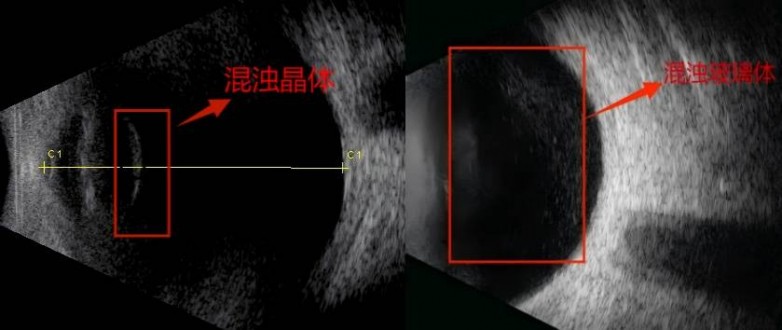

图1示:右眼晶体混浊,左眼晶体透明

图2提示:右眼晶体混浊及玻璃体混浊